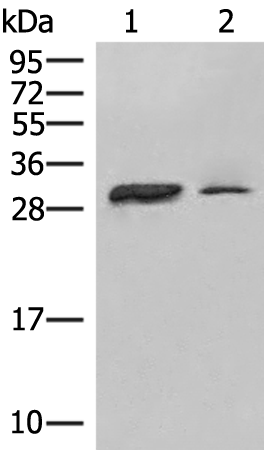

分类: 科研抗体货号: P06646别名: ALT2; GPT 2; MRT49应用: WB反应种属: Human, Mouse